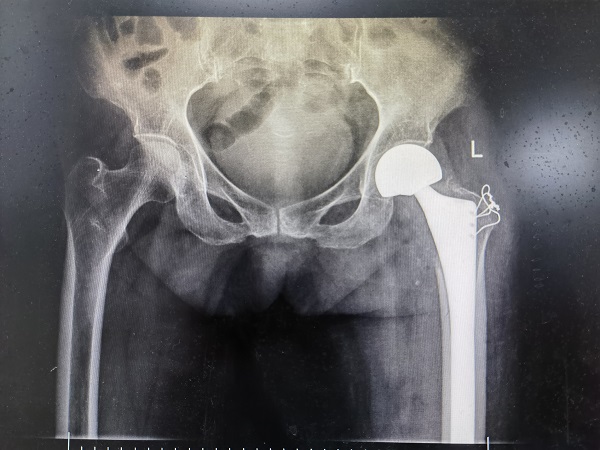

5月5日,在手术室、麻醉科等科室的密切配合下,许立新主任团队为豆奶奶顺利完成了常某的左侧半髋关节置换术,手术全过程仅1小时,术后送回病房进行进一步的观察治疗。 术后第二天,在医护人员的耐心指导下,豆奶奶便可自己下床站立,也终于露出了久违的笑容。